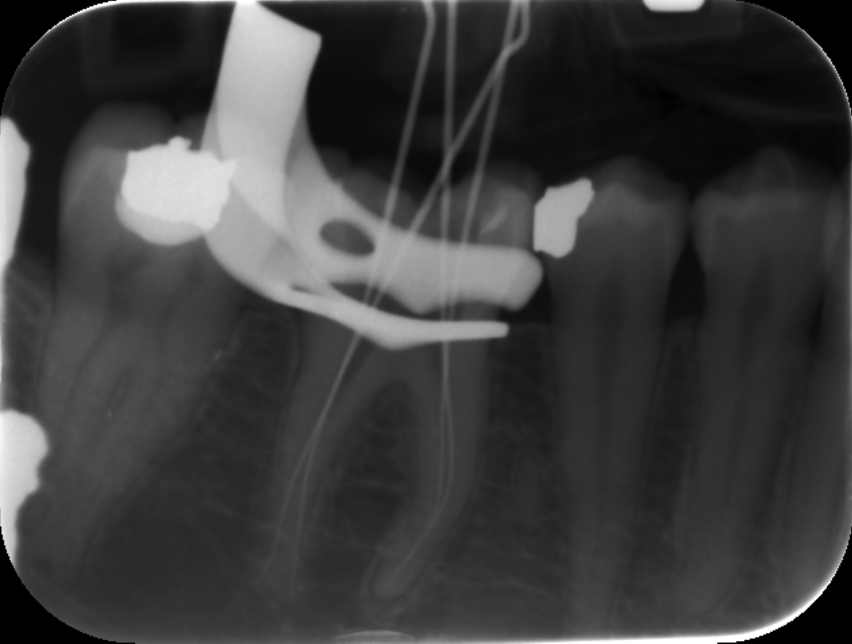

These included team building, communication, photography, endodontics, composite and amalgam restorations, oral surgery, prosthodontics and paediatric dentistry Through these courses I was able to improve on my knowledge and skills from university and implement them in my everyday practice. I have also been keeping a photographic record of my work throughout this year which allows me to reflect on what went well and what I can improve on in the future. space to display your timeline of professional development